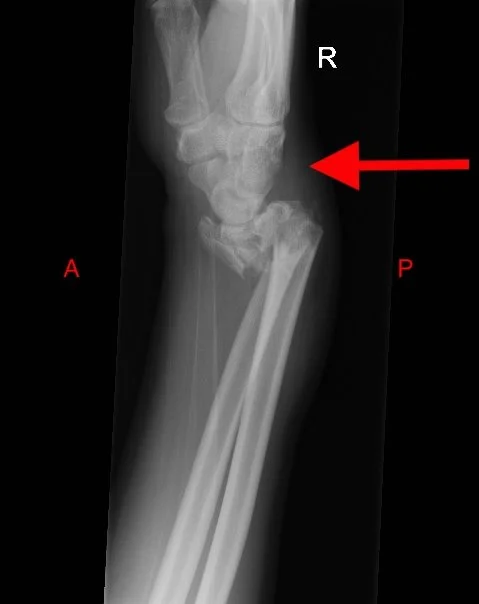

Chauffeur fracture

• Intra-articular fracture of radial styloid process.

• Associated with scaphoid-lunate dissociation.

Case courtesy of Henry Knipe, Radiopaedia.org, rID: 46624 (Chauffeur case)